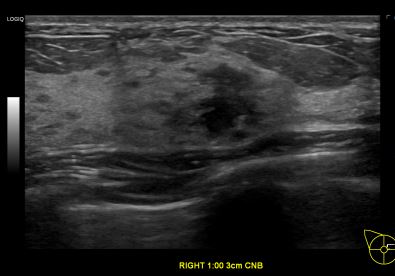

상기환자는 우측유방 만져지는 멍우리있어 내원하신 40대 초반 여성분으로 의심스러운 우측혹 조직검사 시행해 유방암 진단되었습니다.